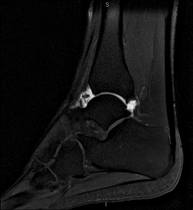

- RM Tobillo

Exploración para el estudio de la articulación y sus frecuentes lesiones de ligamentos (esguinces) así como de la afectación de otras estructuras como el cartílago o el hueso. También es de gran utilidad para diagnosticar alteraciones en el tendón de Aquiles (tendinitis, roturas). Duración de aproximadamente 20 minutos. No emplea radiación ionizante.